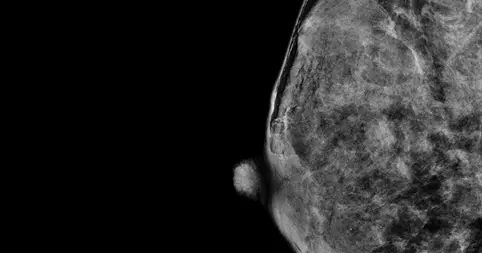

Bi-Rads D

The breast tissue is almost all fibroglandular tissue and is extremely dense.